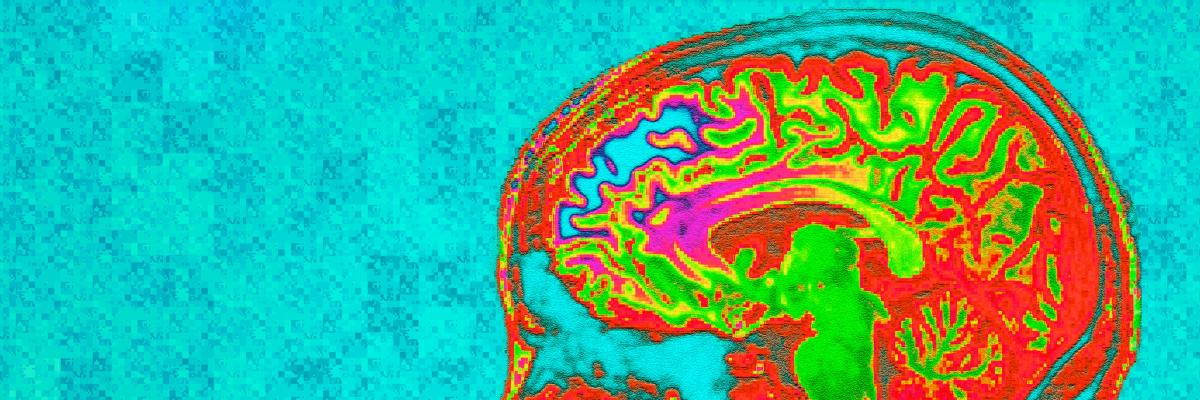

Physiological neuroimaging

Image

banner